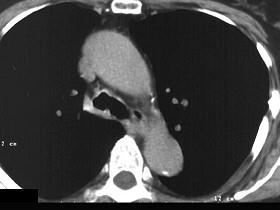

问题 男性,50岁,声音嘶哑近一年,近来感呼吸困难,CT扫描如图所示,请选择正确的描述和结论 ( )

选项 A、考虑为喉气管淀粉样变性 B、考虑气管结核 C、气管后方见软组织肿块 D、肿块内可见致密钙化影 E、喉、气管壁增厚

答案 ACDE